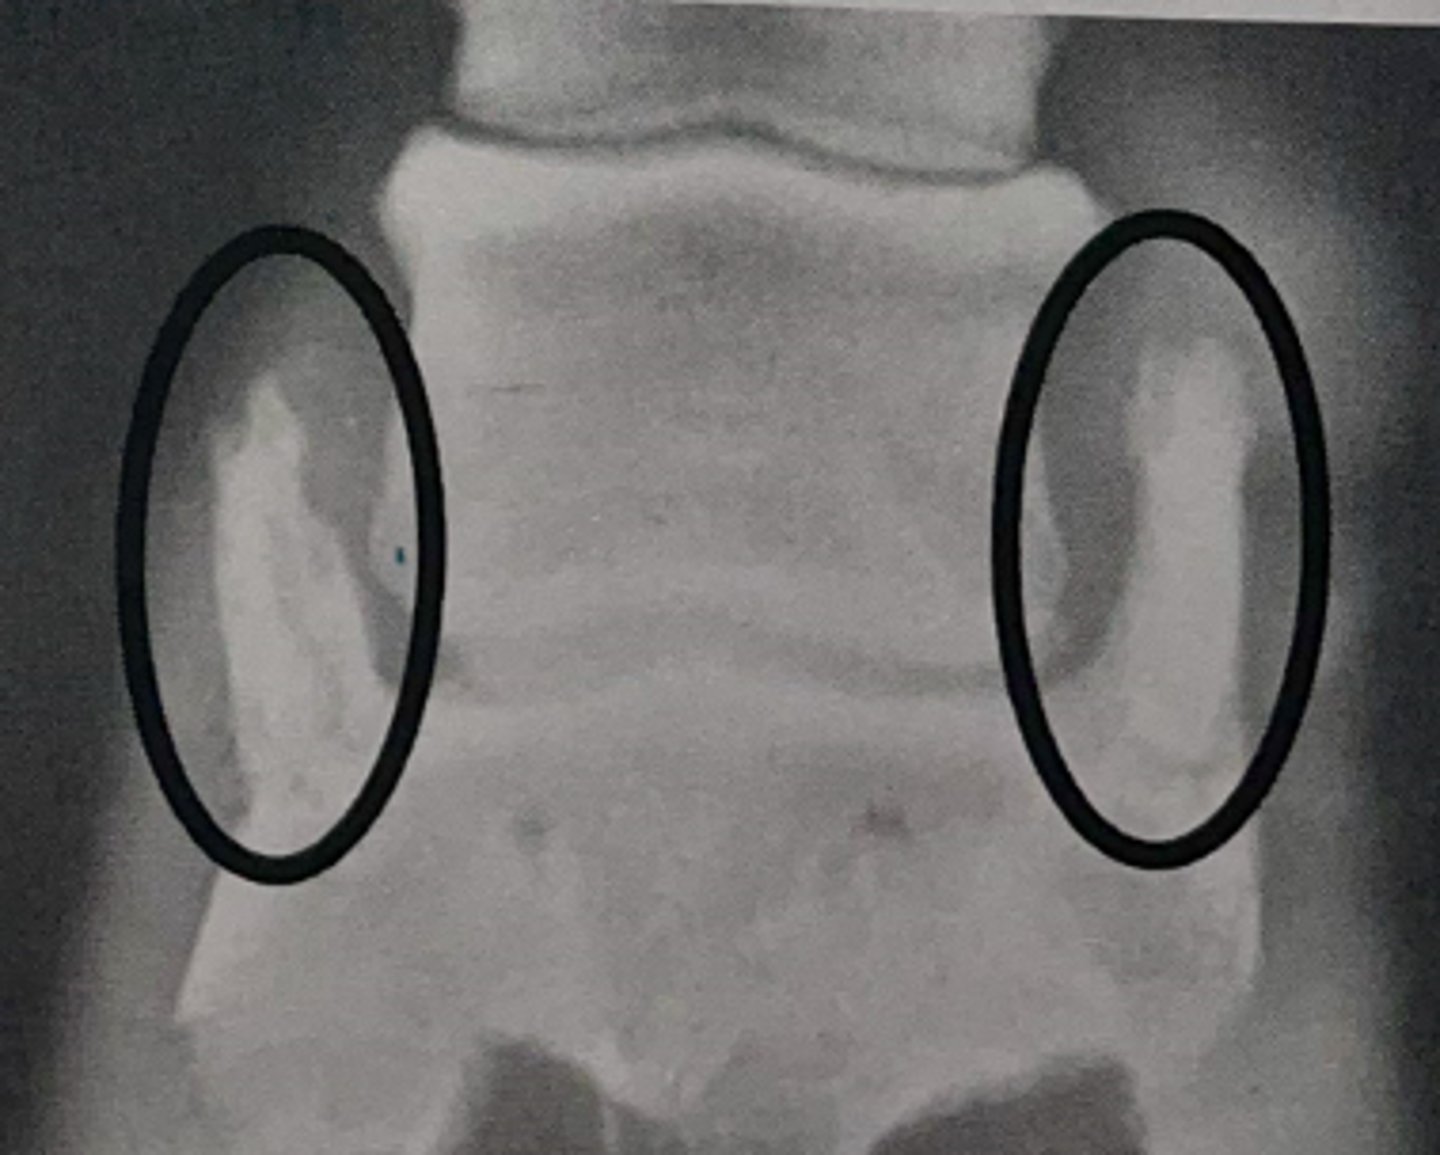

Knowing that the cecum base is in the caudal part of the right abdomen, we know that:

-Picture Left = Horse right

-Picture Right = Horse Left

-Picture top = Cranial

How would you orientate yourself to interpret this picture? Label right, left, and cranial